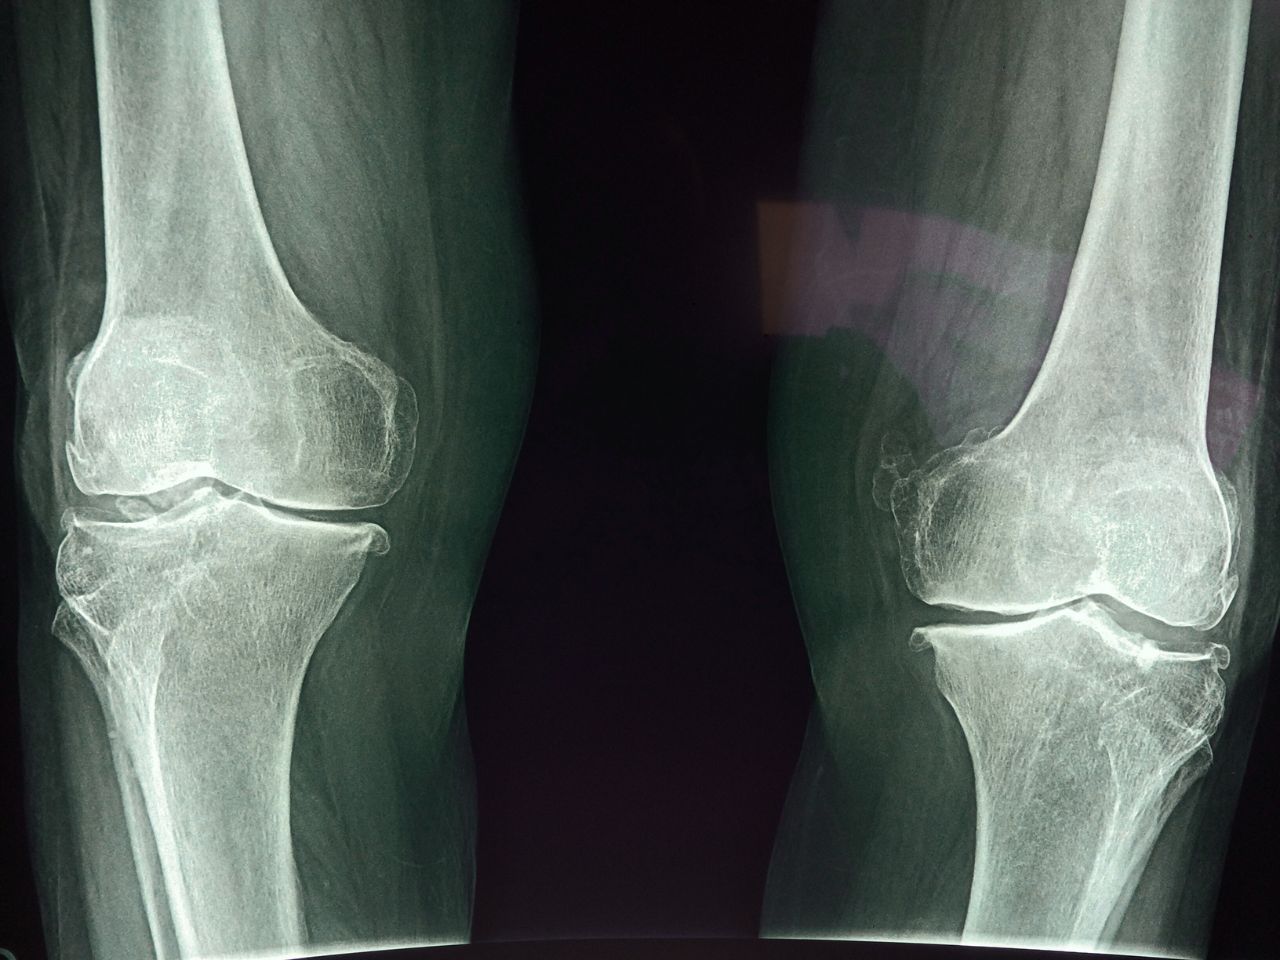

Calcification of soft tissue is an important factor in aging, as it can contribute to a number of age-related conditions and diseases. Calcification refers to the deposition of calcium in soft tissues such as arteries, cartilage, and tendons, which can cause stiffness, loss of elasticity, and reduced function. These signs of aging can be observed in elderly through changes in physical function and posture.

One of the most well-known examples of calcification in aging is atherosclerosis, which is the calcification of arteries that supply blood to the heart. This can lead to reduced blood flow, high blood pressure, and an increased risk of heart disease and stroke. Furthermore a compromised blood flow system is not able to deliver water, oxygen and nutrients to skin cells, making them more prone to aging.Calcification can also occur in other soft tissues, such as tendons and cartilage, which can contribute to joint stiffness and reduced mobility.

Overall, while calcification is a natural process that occurs in the body, excessive calcification can be harmful and contribute to age-related diseases and conditions. Vitamin K2 is the key component of calcification slow down strategy, because it is involved in the regulation of calcium in the body. Specifically, it activates proteins called matrix Gla protein (MGP) and osteocalcin, which are involved in the regulation of calcium metabolism.

Osteopenia often is a natural aging process that starts invisibly in our forties. According to the studies almost half of women and almost third of men aged 50 or more suffer from low bone density. There are numerous dietary strategies to help slow down the progression of osteopenia and subsequent osteoporosis.

Due to so called Calcium Paradox, many of doctors recommend non-calcium dietary interventions, most often based on Vitamin D3, which can help slow down the progression of osteopenia by increasing the absorption of calcium from the intestines. Furthermore osteoblasts, the cells responsible for bone formation, require vitamin D3 to produce osteocalcin, a protein that helps to incorporate calcium into the bone matrix. The osteocalcin, before it can be utilised, must go through carboxylation process, which is facilitated by vitamin K2. Finally, both vitamins have anti-inflammatory action that may reduce the risk of bone loss, because chronic inflammation is associated with increased bone resorption and decreased bone formation.

Vitamin K2 can improve joint health in several ways: Supports cartilage health: Vitamin K2 helps to activate the protein osteocalcin, which is involved in the formation and maintenance of cartilage in joints. This can help to reduce the risk of cartilage degradation and improve joint health. Regulates calcium metabolism: Vitamin K2 helps to regulate calcium metabolism in the body, directing calcium to the bones where it is needed and away from soft tissues, including joints.

Excess calcium in the soft tissues can lead to calcification and joint damage, so Vitamin K2 can help to maintain healthy joint function. Reduces inflammation: Vitamin K2 has anti-inflammatory properties and can help to reduce joint pain and inflammation. This can improve joint mobility and flexibility and help to reduce the risk of joint damage and degeneration. Supports overall joint health: Vitamin K2 helps to maintain overall joint health by supporting the formation and maintenance of strong, healthy bones and reducing the risk of joint damage and degeneration